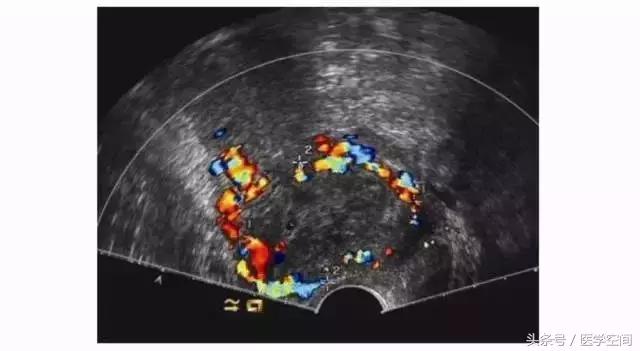

3.2CSP超声误诊的原因及临床后果

CSP超声漏诊进行了药流或人工流产、CSP自发流产不干净的患者,行超声检查时常表现为子宫剖宫产切口瘢痕处的不均质低回声肿块,CDFI在肿块周边常可探及丰富的血流信号(见图5),脉冲多普勒超声检查可探及低阻滋养动脉血流频谱,经验不够者可能会误诊为滋养细胞肿瘤,继而施以化疗。

图5不典型CSP的超声表现